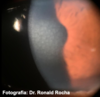

O que é anel de Fleischer?

Anel de ferro presente na base do ceratocone

Fonte: columbia eye